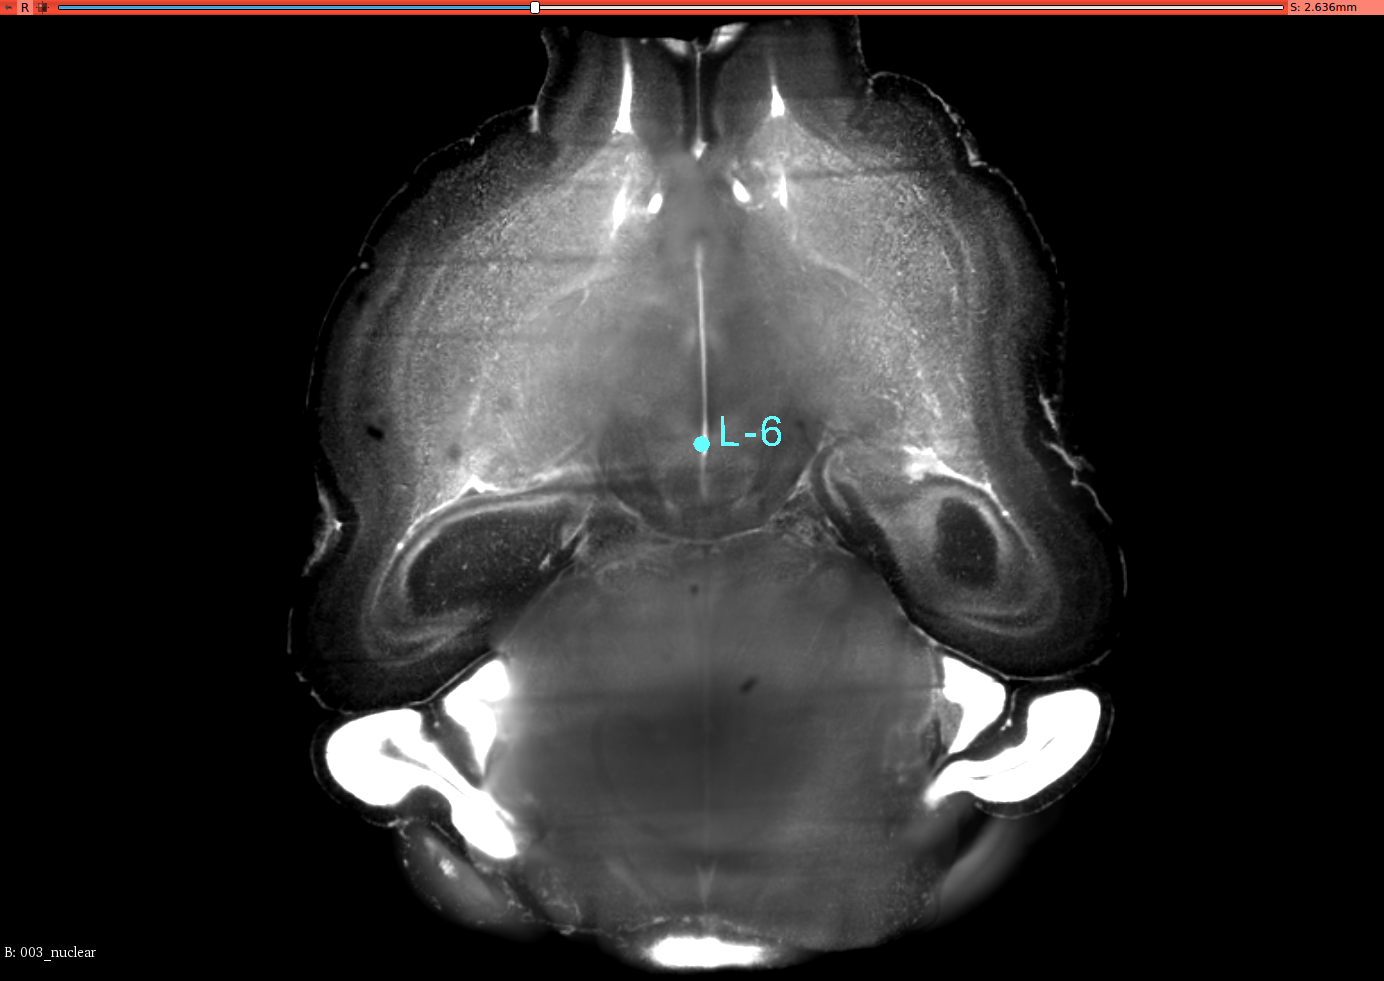

To validate the registration performance of the proposed methods and comparing the baseline methods in a more objective manner, a landmark registration test is conducted. In the CUBIC dataset, three brains are used to test the registration performance. In the landmark test, the same dataset is used for the performance validation. 12 landmarks are selected and all of these landmarks are selected where their positions vary in all three axis. 3D slicer tool is used to select the landmarks for this experiment from the CUBIC brains. A set of selected landmarks are shown in Figure 7. Table 3 shows the results of the 3D landmark registration by proposed InvGAN method and other baseline methods. The Euclidean distance between the registered landmarks and reference landmarks are presented in mm. For optimisation-based ANTS and Elastix tools, the same parameter sets are used to register landmarks selected from moving image and fixed image. After the registration, the output point locations are compared with reference point locations in the fixed image. For the deep-learning-based VoxelMorph and InvGAN, the deformation values in X,Y and Z are extracted from the same voxel location of the selected landmark’s voxel location. After applying deformation to the landmarks, the new position is compared with that of corresponding reference points in the fixed image.

Refer to caption

(a) Brain-1

(b) Segittal View

(c) Coronal View

(d) Corresponding Points in Brain003

(e) Segittal View

(f) Coronal View

(g) Brain-2

(h) Segittal View

(i) Coronal View

(j) Corresponding Points in Brain-3

(k) Segittal View

(l) Coronal View

Figure 7: 3D Landmarks